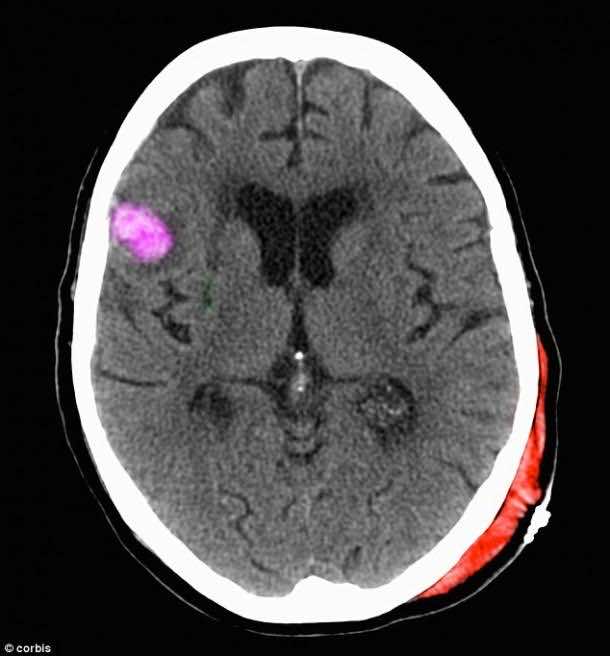

RAM(恢复活动内存)项目是最具创新之一,以及生活DARPA正在改变项目。人民在DARPA希望创建一个大脑植入士兵将恢复记忆的头部严重受伤。这个想法是为了安装植入到士兵的大脑早期记录记忆时发生。以防任何头部严重受伤或大脑会导致记忆丧失,可以恢复记忆芯片系统还原。

目前美国国防部高级研究计划局正在与公司的工作经验与大脑植入物。其中一个是美敦力公司,一直致力于通过帕金森治疗影响的人们通过电子信号发送到大脑。手头的任务并不容易,需要很多时间才能接近现实。第一步需要了解涉及的信号发送到大脑的记忆。

科学家们最近发现了如何研究这些信号和他们来自哪里。目前,我们知道记忆的形成始于信使rna蛋白质,导致神经元连接,导致连接创建的记忆。DARPA计划创建的植入必须区分信号,解释它们,记录整个过程和回放连接。